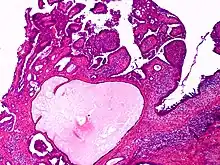

| Apocrine gland carcinoma, papillary type | |

Apocrine gland carcinoma is a cutaneous condition characterized by skin lesions which form in the axilla or anogenital regions.[1]: 670